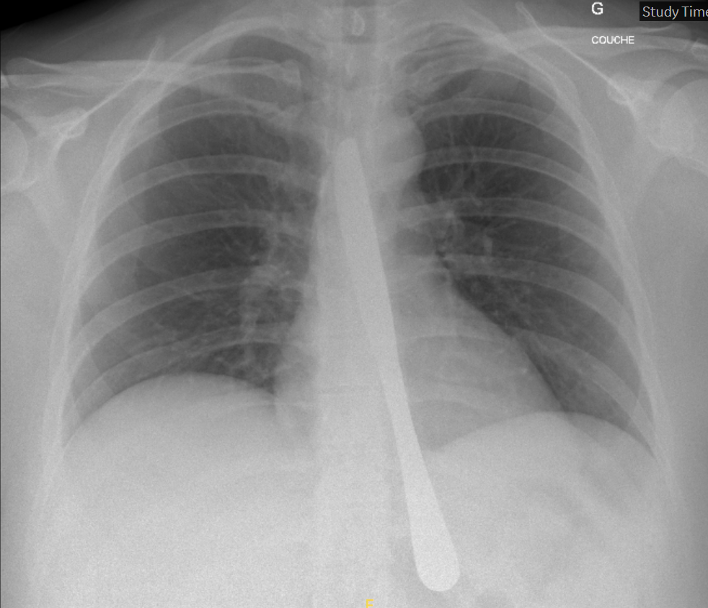

Cette radiographie est celle d’une jeune patiente se présentant aux urgences après récidive d’ingestion volontaire d’un objet métallique dans un contexte de pathologie psychiatrique.

La question qui se pose lorsque le geste est extrêmement répétitif est : peut-on éviter l’endoscopie systématique ?